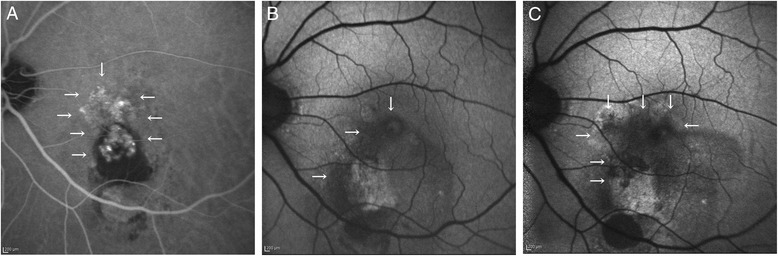

The RPE area overlapping the baseline PCV lesions significantly increased from 0.98 (1.87 mm2) to 2.53 (5.86 mm2) 3 years after the first IVR (P = 0.016), whereas the RPE area not overlapping the baseline PCV lesions changed from 0.21 (0.46 mm2) to 0.40 (0.77 mm2), which did not differ significantly (Fig. 2).

Fig. 2.

Progression of retinal pigment epithelial atrophy (RPE) over polypoidal choroidal vasculopathy (PCV) lesion during ranibizumab therapy. a An indocyanine green angiography (ICGA) image at baseline. White arrows indicate the area of PCV lesions including polypoidal lesions and branching vascular networks. b A fundus autofluorescence (FAF) image at baseline. White arrows indicate the area of RPE atrophy. c A native FAF image at month 36. White arrows indicate the area of RPE atrophy, which enlarges over PCV lesion compared to the baseline area